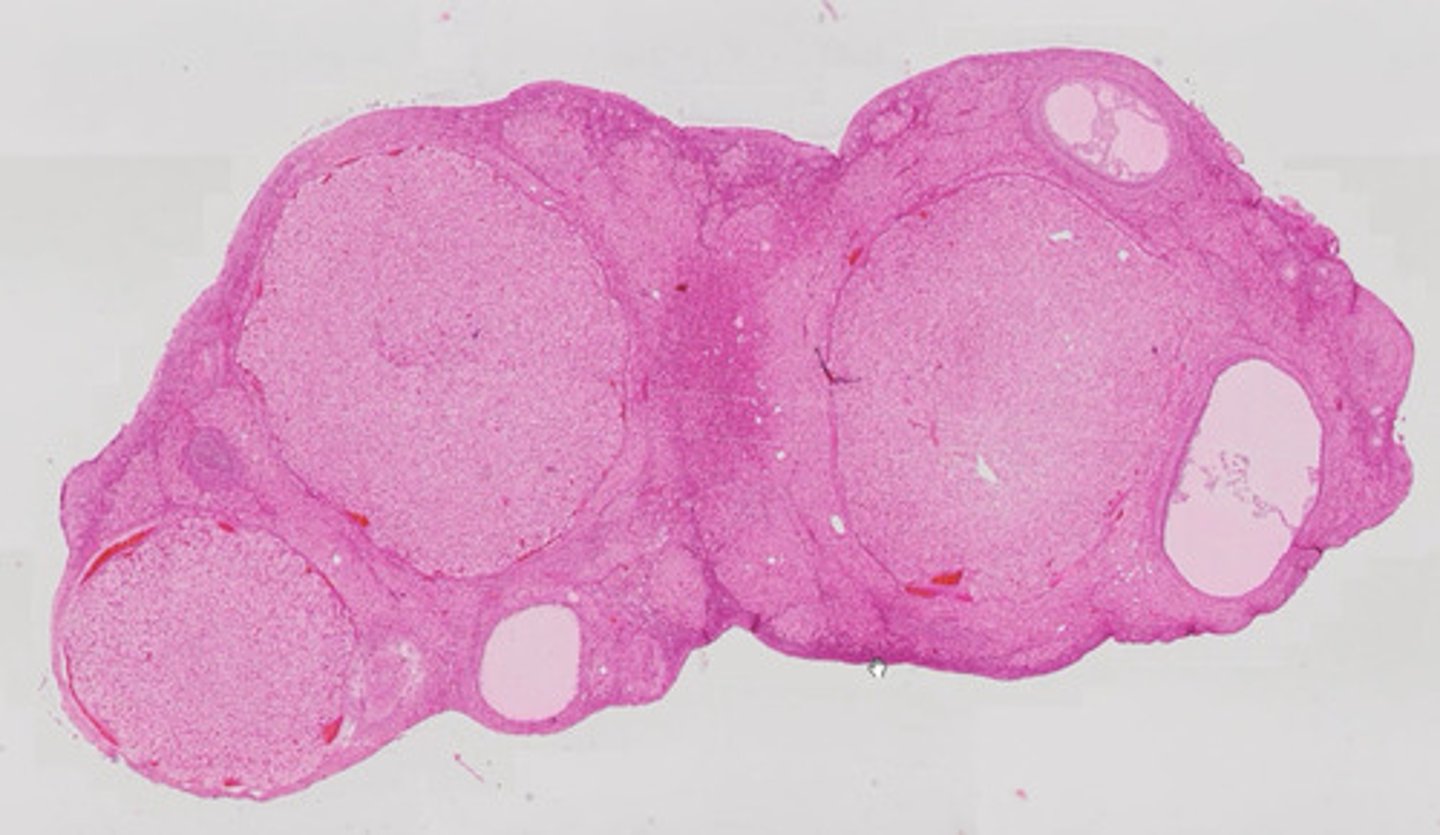

Gruczoł krokowy (met. Mallory)